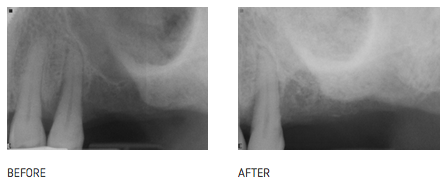

Maxillary sinus floor augmentation (also termed sinus lift, sinus graft, sinus augmentation or sinus procedure) is a surgical procedure where Dr. Newhart aims to increase the amount of bone in the upper jaw bone, in the area where the implants are to be placed. When a natural tooth is lost, the upper jaw begins to shrink and there may not be enough bone height to place an implant without this necessary bone grafting. Over time the jaw bone loses both height and width. Furthermore, the level of the floor of the maxillary sinus gradually becomes lower. Overall, this leads to a loss of volume of bone which is available for implantation of dental implants. The goal of the sinus lift is to graft extra bone into the maxillary sinus, so more bone height is available to support a long and strong dental implant. Dr. Newhart performs this procedure six months prior to dental implant placement and not at the time of dental implant placement. Discomfort and pain are usually minimal and Dr. Newhart has performed this procedure for over 15 years with excellent success. This procedure is needed when there is too much bone loss or the sinus area is too large for him to place the implants using the other crestal approach.